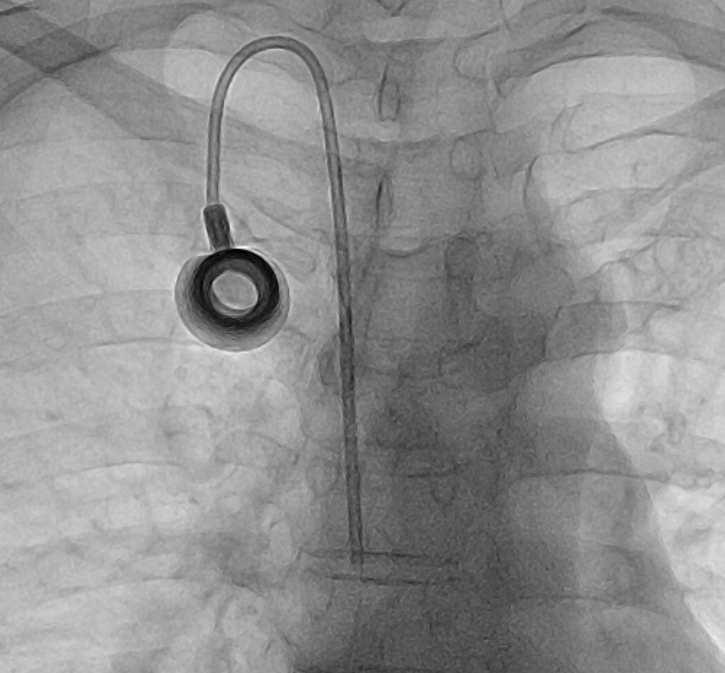

오늘 케모포트 삽입 시술을 하던 중

실제로 케모포트 시술은 숙련된 시술자의 경우 5분에서 10분이면 끝나는 간단한 시술입니다.

환자가 시술 테이블에 눕고 준비를 하는 데 걸리는 시간까지 포함하면 대략 15분에서 20분이면 끝난답니다.

케모포트 삽입에는 테이블에 누운 뒤로 5분~10분이면 시술이 끝난다.